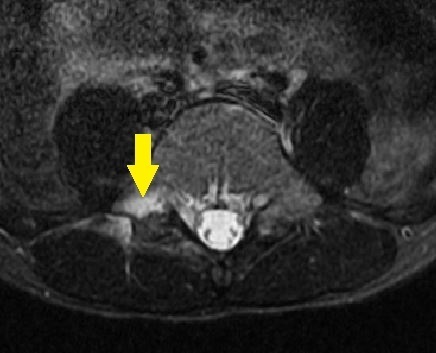

画像検査・診断について

単純レントゲン検査で椎弓・骨年齢の確認、

MRIでは腰椎分離症早期診断を、CT検査(他院依頼)では病期の判定を目的とします。

- 単純レントゲン画像 側面像

- MRI画像

- CT画像

L5左は腰椎分離症終末期